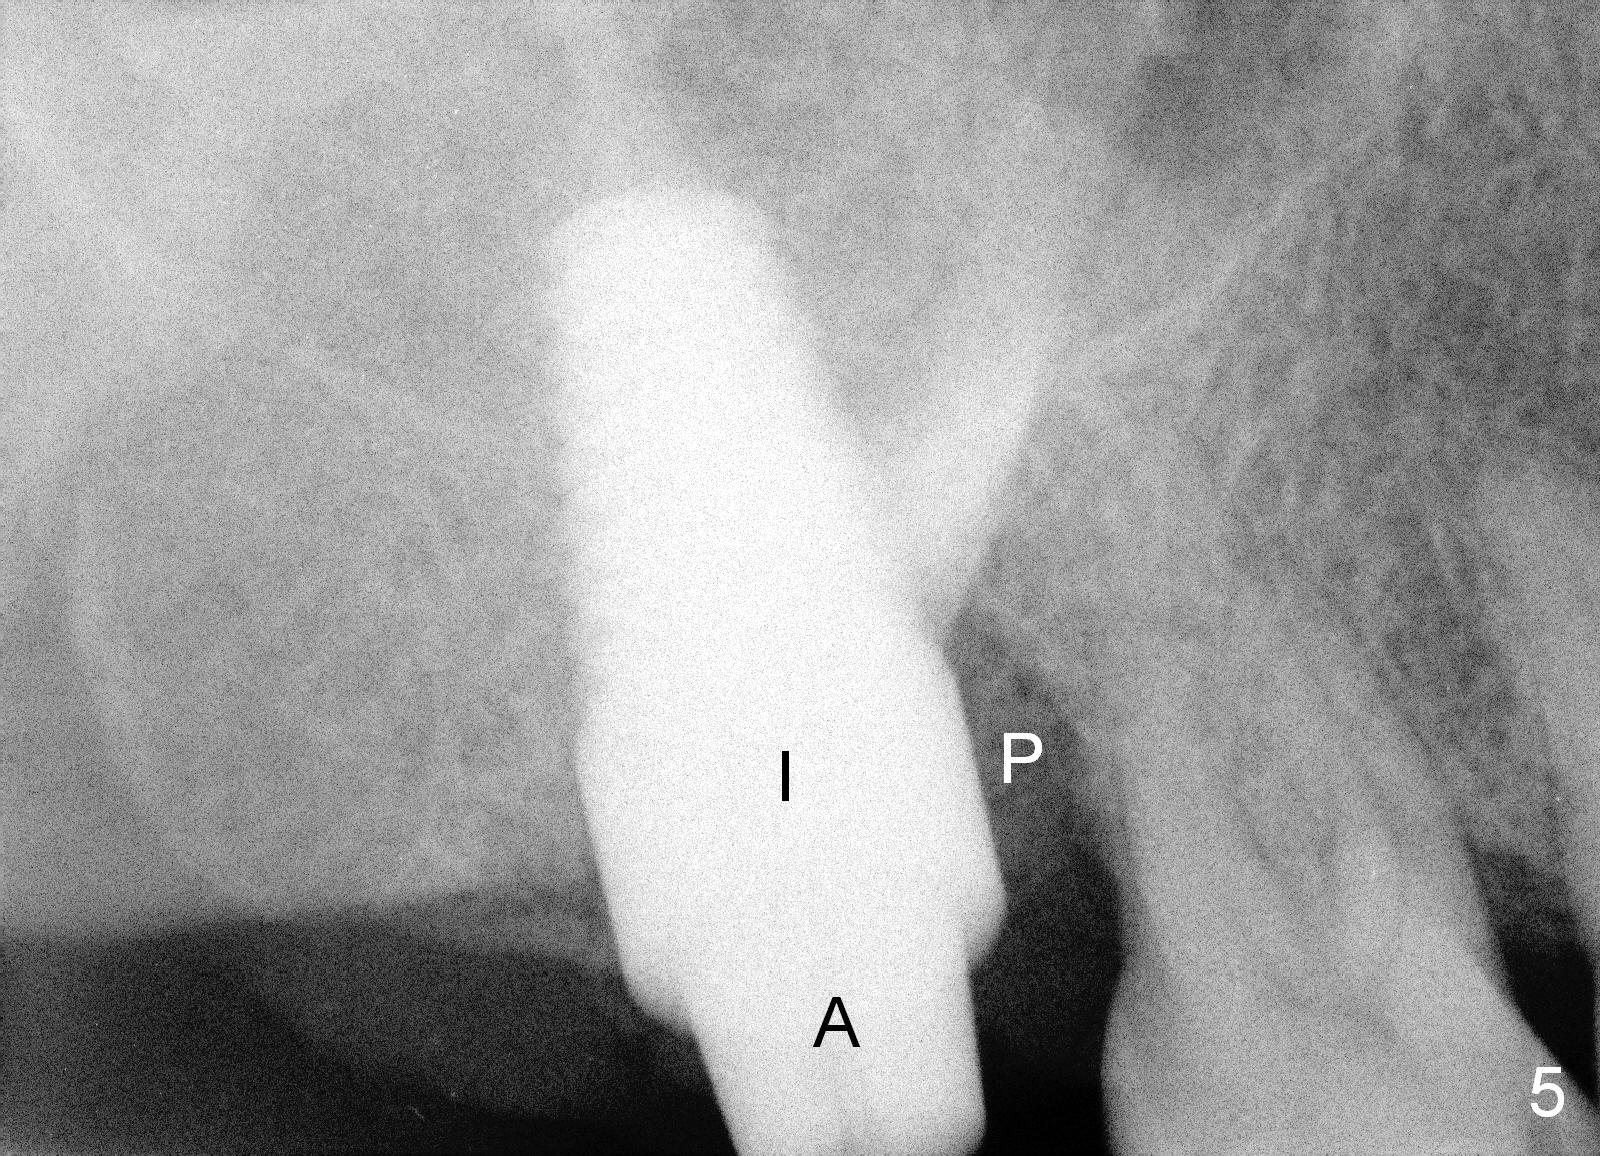

When she returns 7 years later, the tooth #2 has perio abscess with severe bone loss (Fig.3). She refuses to take antibiotic for infection control, but agrees to have immediate implant for #2 because of 1-staged surgery (Fig.5 I: 8x17 mm; A: abutment; P: bone powder (graft)). She is aware of delayed implants at the sites of #15 and 31 later. The bone height at the site of #15 reduces from 12 mm (Fig.4) to 7 mm (Fig.6) in 7 years.

The large implant obliterates the socket mesiodistally (Fig.7); the buccal (B) and palatal (P) gaps are filled with bone graft, which is held in place by an immediate provisional.

The tissue-level implant is placed subgingivally (mesially); insertion torque is 15 Ncm. The same diameter cylindrical implant with larger surface area may achieve higher insertion torque with supragingival margin. The latter is easy for restoration.